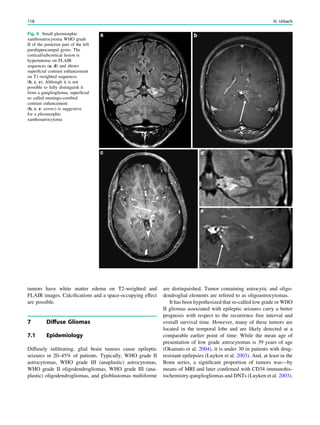

changes have occasionallybeen described and consist of bilateral symmetric lesions with usually reversible cytotoxic edema in the thalami, tegementum of the midbrain, globi pallidi, and dentate nuclei. Despite these changes, patients are usually asymptomatic (Iyer et al. 2011; Simao et al. 2011; Pearl et al. 2009). No specific MRI changes have been described for the newer AED including Levetiracetam, Lamotrigine, Topir- amate, and Gabapentin. References Al-Asmi A, Jansen AC, Badhwar A et al (2005) Familial temporal lobe epilepsy as a presenting feature of choreoacanthocytosis. Epilepsia 46:1256–1263 Arai M, Osaka H (2011) Acute leukoencephalopathy possibly induced by phenytoin intoxication in an adult patient with methylenete- trahydrofolate reductase deficiency. Epilepsia 52:e58–e61 Bader B, Vollmar C, Ackl N, Ebert A, la Fougere C, Noachtar S, Danek A (2011) Bilateral temporal lobe epilepsy confirmed with intracranial EEG electrodes in chorea–acanthocytosis. Seizure 20:340–342 Bartsch T, Deuschl G (2010) Transient global amnesia: functional anatomy and clinical implications. Lancet Neurol 9(2):205–214 Bartsch T, Alfke K, Stingele R, Rohr A, Freitag-Wolf S, Jansen O, Deuschl G (2006) Selective affection of hippocampal CA-1 neurons in patients with transient global amnesia without long- term sequelae. Brain 129(Pt 11):2874–2884 Bilo L, Meo R, Ruosi P, de Leva MF, Striano S (2009) Transient epileptic amnesia: an emerging late-onset epileptic syndrome. Epilepsia 50(Suppl 5):58–61 Brownell B, Hughes JT (1962) The distribution of plaques in the cerebrum in multiple sclerosis. J Neurol Neurosurg Psychiatry 25:315–320 Butler CR, Graham KS, Hodges JR, Kapur N, Wardlaw JM, Zeman AZ (2007) The syndrome of transient epileptic amnesia. Ann Neurol 61:587–598 Butler CR, Bhaduri A, Acosta-Cabronero J, Nestor PJ, Kapur N, Graham KS, Hodges JR, Zeman AZ (2009) Transient epileptic amnesia: regional brain atrophy and its relationship to memory deficits. Brain 132(Pt 2):357–368 Calabrese M, De Stefano N, Atzori M et al (2008) Extensive cortical inflammation is associated with epilepsy in multiple sclerosis. J Neurol 255(4):581–586 Della Marca G, Dittoni S, Pilato F, Profice P, Losurdo A, Testani E. Colicchio S, Gnoni V, Colosimo C, Di Lazzaro V (2010) Teaching neuroimages: transient epileptic amnesia. Neurology 75(10):e47–e48 Dobson-Stone C, Velayos-Baeza A, Filippone LA et al (2004) Chorein detection for the diagnosis of chorea–acanthocytosis. Ann Neurol 56:299–302 Echlin F, Battista J (1963) Epileptiform seizures from chronic isolated cortex. Arch Neurol 9:154–170 Evans MD, Shinar R, Yaari R (2011) Reversible dementia and gait disturbance after prolonged use of valproic acid. Seizure 20(6):509–511 Fisher CM, Adams RD (1964) Transient global amnesia. Acta Neurol Scand 40:1–83 Freemann JL, Coleman LT, Smith LJ, Shield LK (2002) Hemicon- vulsion–hemiplegia–epilepsy syndrome: characteristic early mag- netic resonance imaging findings. J Child Neurol 17:10–16 Gastaut H, Poirier F, Payan H, Salamon G, Toga M, Vigoroux M (1960) H.H.E. syndrome; hemiconvulsions, hemiplegia, epilepsy. Epilepsia 1:418 Geurts JJ, Bo L, Pouwels PJ et al (2005) Cortical lesions in multiple sclerosis: combined postmortem MR imaging and histopathology. AJNR 26:572–577 Grubben B, De Jonghe P, Cras P, Demey HE, Parizel PM (2004) Valproate-induced hyperammonemic encephalopathy: imaging findings on diffusion-weighted MRI. Eur Neurol 52(3):178–181 Hamer HM, Dodel R, Strzelczyk A, Balzer-Geldsetzer M, Reese JP, Schöffski O, Graf W, Schwab S, Knake S, Oertel WH, Rosenow F, Kostev K (2012) Prevalence, utilization, and costs of antiepileptic drugs for epilepsy in Germany—a nationwide population-based study in children and adults. J Neurol 2012 Apr 28 [Epub ahead of print] Huppertz HJ, Kröll-Seger J, Danek A, Weber B, Dorn T, Kassubek J (2008) Automatic striatal volumetry allows for identification of patients with chorea–acanthocytosis at single subject level. J Neural Transm 115:1393–1400 Fig. 8 Sequelae of long-lasting phenytoin therapy in a 38 year old woman who presented with epileptic seizures 22 years ago and was taking phenytoin since this time. Marked cerebellar atrophy (b, c: arrows) and distinct cranial vault thickening (a, b: hollow arrows) are distinct imaging features Other Epilepsy-Associated Diseases and Differential Diagnoses 255

• 255.

Iyer RS, ChaturvediA, Pruthi S, Khanna PC, Ishak GE (2011) Medication neurotoxicity in children. Pediatr Radiol 41:1455–1464 Jokeit H, Okujava M, Woermann FG (2001) Carbamazepine reduces memory induced activation of mesial temporal lobe structures: a pharmacological fMRI-study. BMC Neurol 18:1–6 Jung HH, Danek A, Walker RH (2011) Neuroacanthocytosis syn- dromes. Orphanet J Rare Dis 6:68 Kallenberg K, Dehnert C, Dörfler A, Schellinger PD, Bailey DM, Knauth M, Bärtsch PD (2008) Microhemorrhages in nonfatal high- altitude cerebral edema. J Cereb Blood Flow Metab 28:1635–1642 Kapur N (1993) Transient epileptic amnesia—a clinical update and a reformulation. J Neurol Neurosurg Psychiat 56:1184–1190 Kelley BJ, Rodriguez M (2009) Seizures in patients with multiple sclerosis: epidemiology, pathophysiology and management. CNS Drugs 23:805–815 Kim SS, Chang KH, Kim ST et al (1999) Focal lesion in the splenium of the corpus callosum in epileptic patients: antiepileptic drug toxicity? AJNR Am J Neuroradiol 20:125–129 Laxer KD, Robertson LT, Julien RM, Dow RS (1980) Phenytoin: relationship between cerebellar function and epileptic discharges. Adv Neurol 27:415–427 Lebrun C (2006) Epilepsy and multiple sclerosis. Epileptic Disord 8:555–558 Luef G, Chemelli A, Birbamer G, Aichner F, Bauer G (1994) Phenytoin overdosage and cerebellar atrophy in epileptic patients: clinical and MRI findings. Eur Neurol 34(Suppl 1):79–81 Nakada T, Kwee IL, Fujii Y, Knight RT (2005) High-field, T2-reversed MRI of the hippocampus in transient global amnesia. Neurology 64:1170 Nelles M, Bien CG, Kurthen M, von Falkenhausen M, Urbach H (2006) Transient splenium lesions in presurgical epilepsy patients: incidence and pathogenesis. Neuroradiology 48:443–448 Nicholas JM, Ridsdale L, Richardson MP, Ashworth M, Gulliford MC (2012) Trends in antiepileptic drug utilisation in UK primary care 1993–2008: Cohort study using the General Practice Research Database. Seizure 21(6):466–470 Nicoletti A, Sofia V, Biondi R et al (2003) Epilepsy and multiple sclerosis in Sicily: a population-based study. Epilepsia 44: 1445–1448 Nyquist PA, Cascino GD, Rodrigue M (2001) Seizures in patients with multiple sclerosis seen at Mayo Clinic, Rochster, Minn, 1990–1998. Mayo Clin Proc 76:983–986 Nyquist PA, Cascino GD, McClelland RL et al (2002) Incidence of seizures in patients with multiple sclerosis: a population-based study. Mayo Clin Proc 77:910–912 Olafsson E, Benedikz J, Hauser WA (1999) Risk of epilepsy in patients with multiple sclerosis: a population-based study in Iceland. Epilepsia 40:745–747 Pearl PL, Vezina LG, Saneto RP et al (2009) Cerebral MRI abnormalities associated with vigabatrin therapy. Epilepsia 50:184–194 Schaffer AJ (1927) The etiology of infantile acquired hemiplegia. Arch Neurol Psychiatry 18:323 Scheid R, Bader B, Ott DV, Merkenschlager A, Danek A (2009) Development of mesial temporal lobe epilepsy in chorea–acantho- cytosis. Neurology 73:1419–1422 Sedlaczek O, Hirsch JG, Grips E, Peters CNA, Gass A, Wöhrle J, Hennerici M (2004) Detection of delayed focal MR changes in the lateral hippocampus in transient global amnesia. Neurology 62:2165 Simao GN, Zarei Mahmoodabadi S, Snead OC, Go C, Widjaja E (2011) Abnormal axial diffusivity in the deep gray nuclei and dorsal brain stem in infantile spasm treated with vigabatrin. AJNR Am J Neuroradiol 32:199–203 Specht U, May TW, Rohde M, Wagner V, Schmidt RC, Schütz M, Wolf P (1997) Cerebellar atrophy decreases the threshold of carbamazepine toxicity in patients with chronic focal epilepsy. Arch Neurol 54(4):427–431 Velayos-Baeza A, Vettori A, Copley RR, Dobson-Stone C, Monaco AP (2004) Analysis of the human VPS13 gene family. Genomics 84:536–549 Viveiros CD, Alvarenga RM (2010) Prevalence of epilepsy in a case series of multiple sclerosis patients. Arq Neuropsiquiatr 68:731– 736 Zeman AZ, Boniface SJ, Hodges JR (1998) Transient epileptic amnesia: a description of the clinical and neuropsychological features in 10 cases and a review of the literature. J Neurol Neurosurg Psychiatry 64:435–443 256 H. Urbach

• 256.

Postsurgical MRI Marec vonLehe and Horst Urbach Contents 1 Extended Lesionectomy ...................................................... 257 1.1 Indications.............................................................................. 257 1.2 Surgical Techniques .............................................................. 257 1.3 Imaging .................................................................................. 257 2 Amygdalohippocampectomy and Anterior Temporal Lobectomy ............................................................................ 258 2.1 Indications.............................................................................. 258 2.2 Surgical Techniques .............................................................. 258 2.3 Imaging .................................................................................. 260 3 Functional Hemispherectomy or Hemispherotomy......... 260 3.1 Indications.............................................................................. 260 3.2 Surgical Techniques .............................................................. 261 3.3 Imaging .................................................................................. 263 4 Corpus Callosotomy ............................................................ 263 4.1 Indications.............................................................................. 263 4.2 Surgical Technique................................................................ 264 4.3 Imaging .................................................................................. 264 5 Multiple Subpial Transsections.......................................... 265 5.1 Indications.............................................................................. 265 5.2 Surgical Technique................................................................ 265 5.3 Imaging .................................................................................. 265 References...................................................................................... 265 Abstract The goal of the surgical procedure is to resect or disconnect the epileptogenic area, defined as the cortex area indispensable for the generation of seizures. The epileptogenic area is—among others and, depending on the pathological substrate of the lesion—often larger than the epileptogenic lesion itself, so that extended lesionectomy (e.g., with a 5–10-mm rim of perilesional tissue) is performed. Several standardized neurosurgical procedures have been developed and refined to date. 1 Extended Lesionectomy 1.1 Indications Focal epilepsy caused by a cortical lesion is a heterogeneous group of disorders that arises from a variety of pathologies and from different anatomical areas. The presurgical workup determines the focal origin (a critical prerequisite) and the resection strategy. In addition to the evaluation of clinical parameters, different imaging modalities are applied; in some cases, an invasive workup with implanted electrodes is nec- essary. In each case, the spatial relationship of the lesion to eloquent cortex areas is the most important parameter influ- encing the surgical strategy (Schramm and Clusmann 2008). The decision making is—as always in epilepsy sur- gery—a multidisciplinary process and at the end results in the best possible counseling of the patient about the benefits (chance of freedom from seizures) and risks (neurological and neuropsychological deficits). 1.2 Surgical Techniques The aim of epilepsy surgery is to resect as much tissue as deemed necessary to provide complete seizure relief with- out causing unacceptable permanent neurological damage. M. von Lehe Department of Neurosurgery, University of Bonn, Bonn, Germany H. Urbach (&) Department of Neuroradiology, University Hospital Freiburg, Germany e-mail: horst.urbach@uniklinik-freiburg.de H. Urbach (ed.), MRI in Epilepsy, Medical Radiology. Diagnostic Imaging, DOI: 10.1007/174_2012_775, Ó Springer-Verlag Berlin Heidelberg 2013 257

• 257.

The typical extendedlesionectomy includes a 5–10-mm rim of ‘‘unaffected tissue.’’ In some cases of well-circumscribed lesions (e.g., focal cortical dysplasia type IIB), just a pure lesionectomy without extension (but possibly combined with MST; see below) is feasible due to the close rela- tionship with eloquent cortex areas. Principles of the resection are independent of the pathology or location and can be done even in highly elo- quent areas with adequate safety (von Lehe et al. 2009). After identification of the area to be removed (neuronavi- gation, electrocorticography, and results of invasive EEG are determinants), the subpial removal of the gray matter is performed. The sulci with the passing vascular structures are carefully preserved as well as the surrounding cortical areas, as such injury may cause neurological deficits or seizures itself. The removal of underlying white matter will not improve seizure control and may cause deficits due to injury to passing fibers. In neocortical temporal lesionectomies, an extension may include the resection of the mesial structures (hippo- campus, amygdala), depending on the presurgical workup. 1.3 Imaging The extent of resection should be ideally controlled with postsurgical MRI. The goal is to prove the complete resection of the lesion, to exclude surgical complications, and to serve as the base for follow-up MRI imaging in case neoplastic lesions occur. If there are no clinical reasons for immediate postsurgical MRI, it is ideally performed about 3 months after surgery, when acute surgery-related changes have regressed (See Fig. 1). 2 Amygdalohippocampectomy and Anterior Temporal Lobectomy 2.1 Indications Mesial temporal lobe epilepsy is the most frequent form of refractory focal epilepsy, and hippocampal sclerosis is the typical underlying histopathological substrate. In addition to extended lesionectomies in the temporal lobe, there are so- called standard resections, such as the anterior temporal lobectomy and the selective amygdalohippocampectomy. With improved imaging techniques and more experience in presurgical workup, limited surgical strategies have evolved over the last decades (Clusmann et al. 2002, 2006). Never- theless, standard temporal lobectomy is still used in many centers to resect the epileptogenic focus. 2.2 Surgical Techniques The classic temporal lobectomy (‘‘two-third anterior lobec- tomy’’) usually combines neocortical resection with removal of the mesial structures (Nayel et al. 1991). The typical length of the resection from the temporal pole is 5.5 cm in the nondominant hemisphere and 4.5 cm in the dominant hemisphere. Usually, the surgical technique comprises two steps: First, the neocortical block and the underlying white matter are removed, with subsequent opening of the temporal horn of the lateral ventricle. After that, mesial structures (uncus, amygdala, hippocampus, and parahippocampal gyrus) are removed by subpial dissection (Fig. 2). Fig. 1 Lesionectomy of an FCD IIB of the right postcentral gyrus. a shows a bottom of sulcus dysplasia with the funnel-shaped hyperintensity tapering to the lateral ventricle (a arrow), b and c the resection cavity. Arrows in c point to the hand knobs of the precentral gyri 258 M. von Lehe and H. Urbach